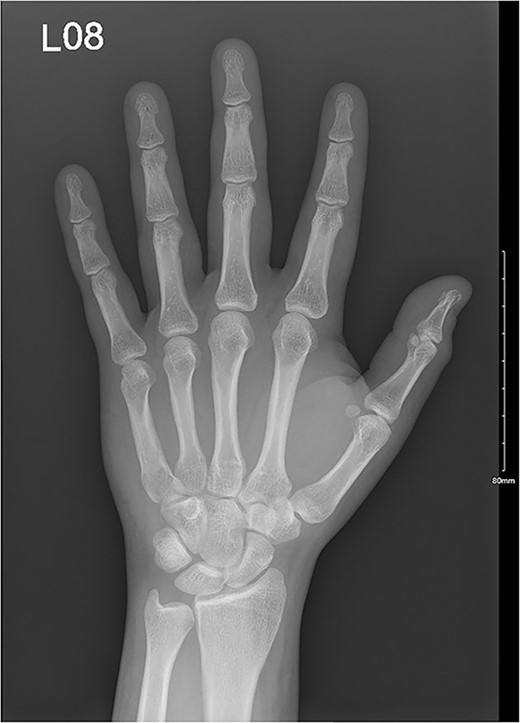

A 32-year-old male presented to the emergency department with a painful, discolored, and edematous left thumb following spontaneous deployment of his automobile’s airbag. On physical examination, the thumb’s range of motion (ROM) was reduced because of pain. Radiography showed a tuft fracture of the thumb’s distal phalanx (Fig. 1). The patient was managed conservatively with a Zimmer splint and followed-up 1 week later. Magnetic resonance imaging (MRI) was obtained to assess for the presence of ligamentous injury showed complete tearing and proximal retraction of the distal attachment of the ulnar collateral ligament in (Fig. 2), so the patient was given a thumb spica and was booked for surgery. In the operating room, the ulnar collateral ligament was identified and was indeed completely avulsed from its distal attachment site. The ligament was repaired using the Kessler tendon repair maneuver, ultimately ending with the thumb flexed 30° at the metacarpophalangeal (MCP) joint. This patient was followed-up for 103 days after his first presentation. On his final clinic visit, the thumb was stable, the wound was fully healed, and full ROM was regained.

Complete tear of ulnar collateral ligament with significant proximal retraction.